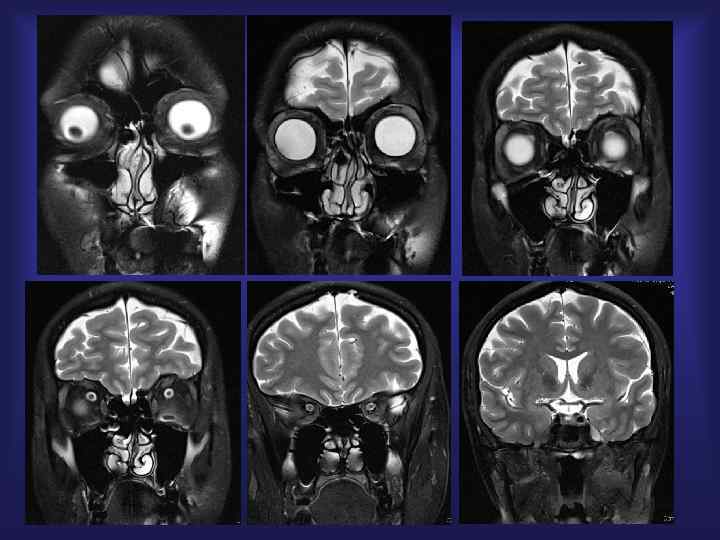

Менингиома • Встречаемость 15 -20% всех опухолей г. м. • Признаки КТ - гиперденс. 70 -75% • МРТ – изоинтенсивно с серым веществом • Накопление контраста – выраженное, гомогенное

Схема внемозгового расположения опухоли A. Osborn, 2005

Внемозговое расположение: ликворная щель, дислокация мозга, периф. сосуды

Парасагиттальная менингиома

Парасагиттальная менингиома МРТ + Gd